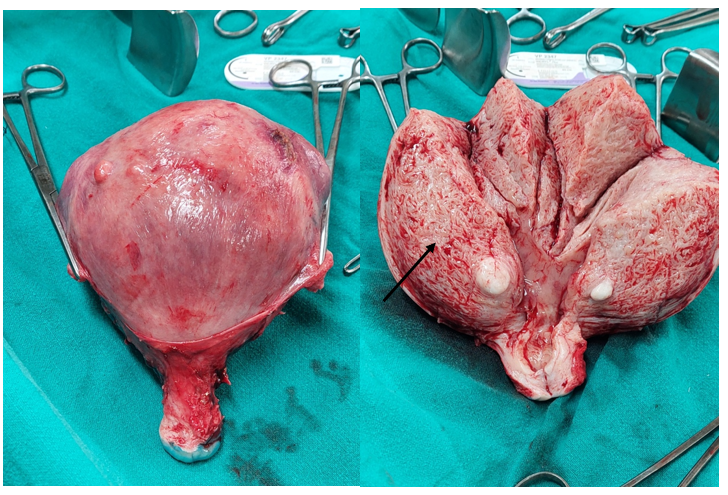

Arterial Stiffness in Pregnant with Non-Alcoholic Fatty Liver Disease During 4th to 31th Gestational Week Follow-Up: A Case Report of Preterm Birth

Avramovska Maja, Poposki Vlatko, Stefan Talev, Stoilova Snezana, Mira Mladenovska, Kosta Sotiroski, Vesna Shiklovska and Avramovski Petar.